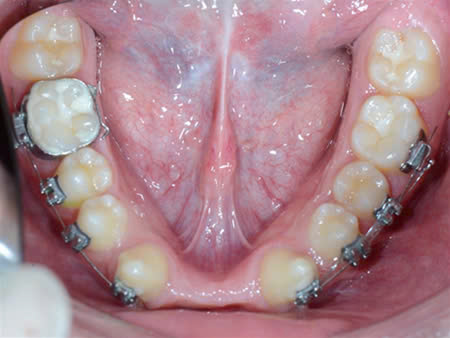

Kết hợp giữa chỉnh nha và phục hình implant: để sắp đều răng và phục hình các răng thiếu trên cung hàm.

Ở nha khoa Như Ngọc, chúng tôi đang phối hợp điều trị và theo dõi cho bệnh nhân nhân loạn sản ngoại bì.

Đối với điều trị răng cho các bé từ giai đoạn ban đầu hàm giả tháo lắp giúp phục hồi chức năng ăn nhai cũng như phát âm, giao tiếp cho trẻ 1 cách tốt nhất.